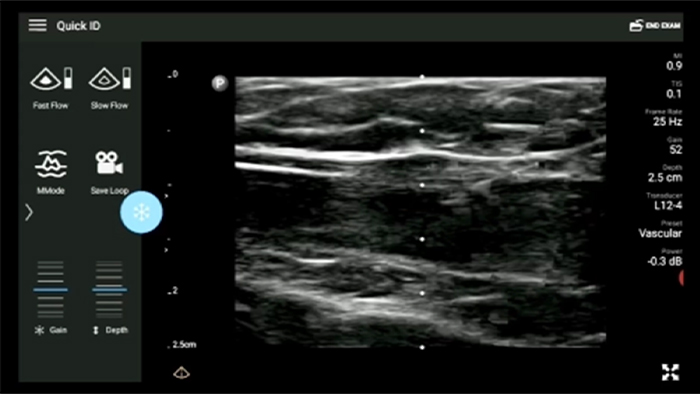

De Lumify draagbare echografieoplossing voor loco regionale anesthesiologie helpt u bij het visualiseren van de omliggende zenuwen, vaten, omliggende weefsels en naald-in situ tijdens de procedure.

Lumify helpt u de plaatsing van de naalden, de omringende zenuwen, vaten en fascia-vlakken duidelijk te visualiseren.